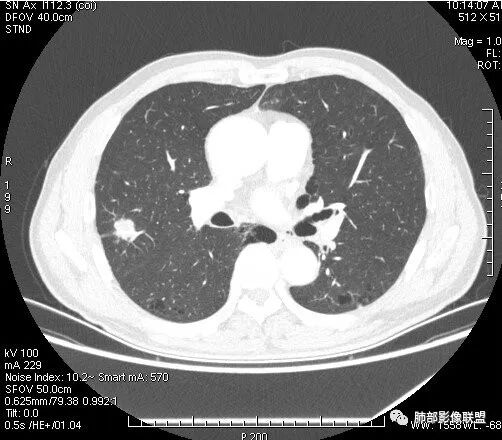

影像学改变:

1.右肺上叶后段类圆形结节影,密度不均,有坏死空洞,坏死比较彻底,内外壁都较清楚。

2.病灶有浅切迹,没有深分叶,毛刺大多细长且柔软。

3.可见棘状突起及胸膜牵拉,但未见胸膜凹陷。

什么意思?结节影有牵拉的动作,但似乎“出工不出力”,收缩力羸弱!

4.病灶轻到中度强化。病灶内血管走行较完好,病灶旁血管局部显示粗大。

5.支气管关系不确定。

6.灶周见小结节影(卫星灶),边界不甚清晰。

1.结核是常见的,坏死也够彻底,有卫星灶。疑问在于血管为什么不受累?

2.其他的慢性炎症。边界清楚符合慢性。慢性肺脓肿、隐球菌感染、奴卡菌感染等等都可以。可惜缺乏病原学依据。